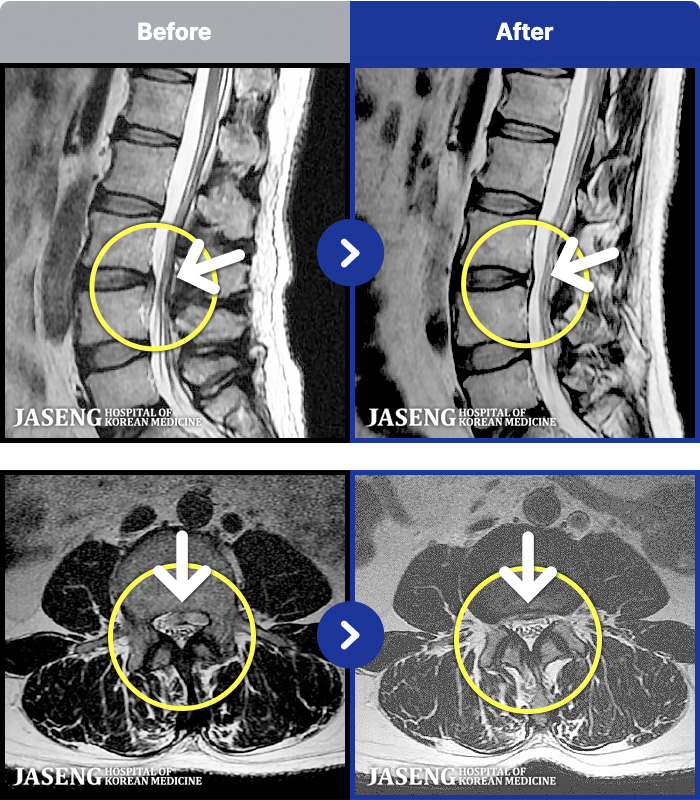

- MRI ġ

MRI ġ

63 MRI ũ ʸ Ȯϼ.